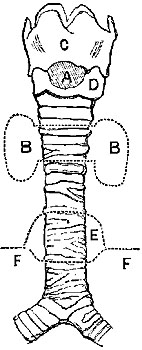

The patient lying down with the shoulders raised and head thrown well back, the sternal attachment of the right sterno-mastoid must be very freely exposed. This may be done by an incision (Plate I. fig. 7) along its anterior edge from the upper edge of the sternum, as far as may be necessary; another about the same length along the upper edge of the clavicle, will meet the former at an acute angle, and will include a triangular flap of skin, which must be carefully dissected up. The sternal, and probably a portion of the clavicular attachment of the right sterno-mastoid, must then be cautiously divided. This being done, the sterno-hyoid and sterno-thyroid muscles require division immediately above their sternal attachments.

A dense process of cervical fascia (just becoming thoracic) now covers the vessel, binding it on the right side to the right innominate vein, and on the left maintaining the relation of the innominate artery to the trachea. The inferior thyroid veins lie on this fascia, and must be drawn aside, not cut. The fascia is then to be scraped through very cautiously, exposing the root of the right carotid, which, being traced downwards, will lead to the innominate. The following parts lie in close relation to the vessel at the point of ligature, and must be avoided:—1. The left innominate vein crosses the artery in front from left to right, and must be drawn down. 2. The right innominate vein and right pneumogastric are in close contact with the artery on the right side; to avoid them the aneurism-needle must be entered on the outside (right of the vessel). 3. The apex of the right pleura and the trachea are in close contact behind, requiring the point of the needle to be kept close to the artery in bringing the thread round.

Right Subclavian.—The innominate artery divides into the right subclavian and right carotid exactly behind the sterno-clavicular articulation. The right subclavian extends from this point in an arched form across the neck, between the scalene muscles, over the apex of the pleura, till, passing under cover of the clavicle, it changes its name to axillary at the lower end of the first rib. For convenience of description, the artery is divided into three parts, which have very various anatomical relations, and differ from each other much in their amenability to surgical treatment by ligature. The anterior scalenus muscle defines the three parts, the{34} first extending to the inner border of the muscle, the second being concealed by the muscle, and the third reaching from its outer border to the lower border of the first rib.

Branches of the Subclavian.—While the deep relations of pleura, veins, and nerves can be noticed under the head of each operation in detail, one anatomical point must never be forgotten as influencing very much the success of all surgical interference with the subclavian arteries—i.e. the branches given off. To give any chance of success in the application of a ligature to such a large vessel, so near the heart, a large portion of artery free from branches is required, that the clot may be long, firm, and undisturbed. The first part of the subclavian gives off the vertebral, thyroid axis, and internal mammary; the second, the superior intercostal; while the third part has in most cases no branch whatever. In these anatomical differences we find the reason for the almost invariable fatality resulting on any interference with the first and second parts, and the comparative safety of ligature of the third part, without requiring to account for the difference on other grounds, such as depth of part, importance of nervous relations, or nearer proximity to the heart.

Ligature of Subclavian.—Third Part.—For this comparatively common operation, various methods of procedure have been suggested and employed.